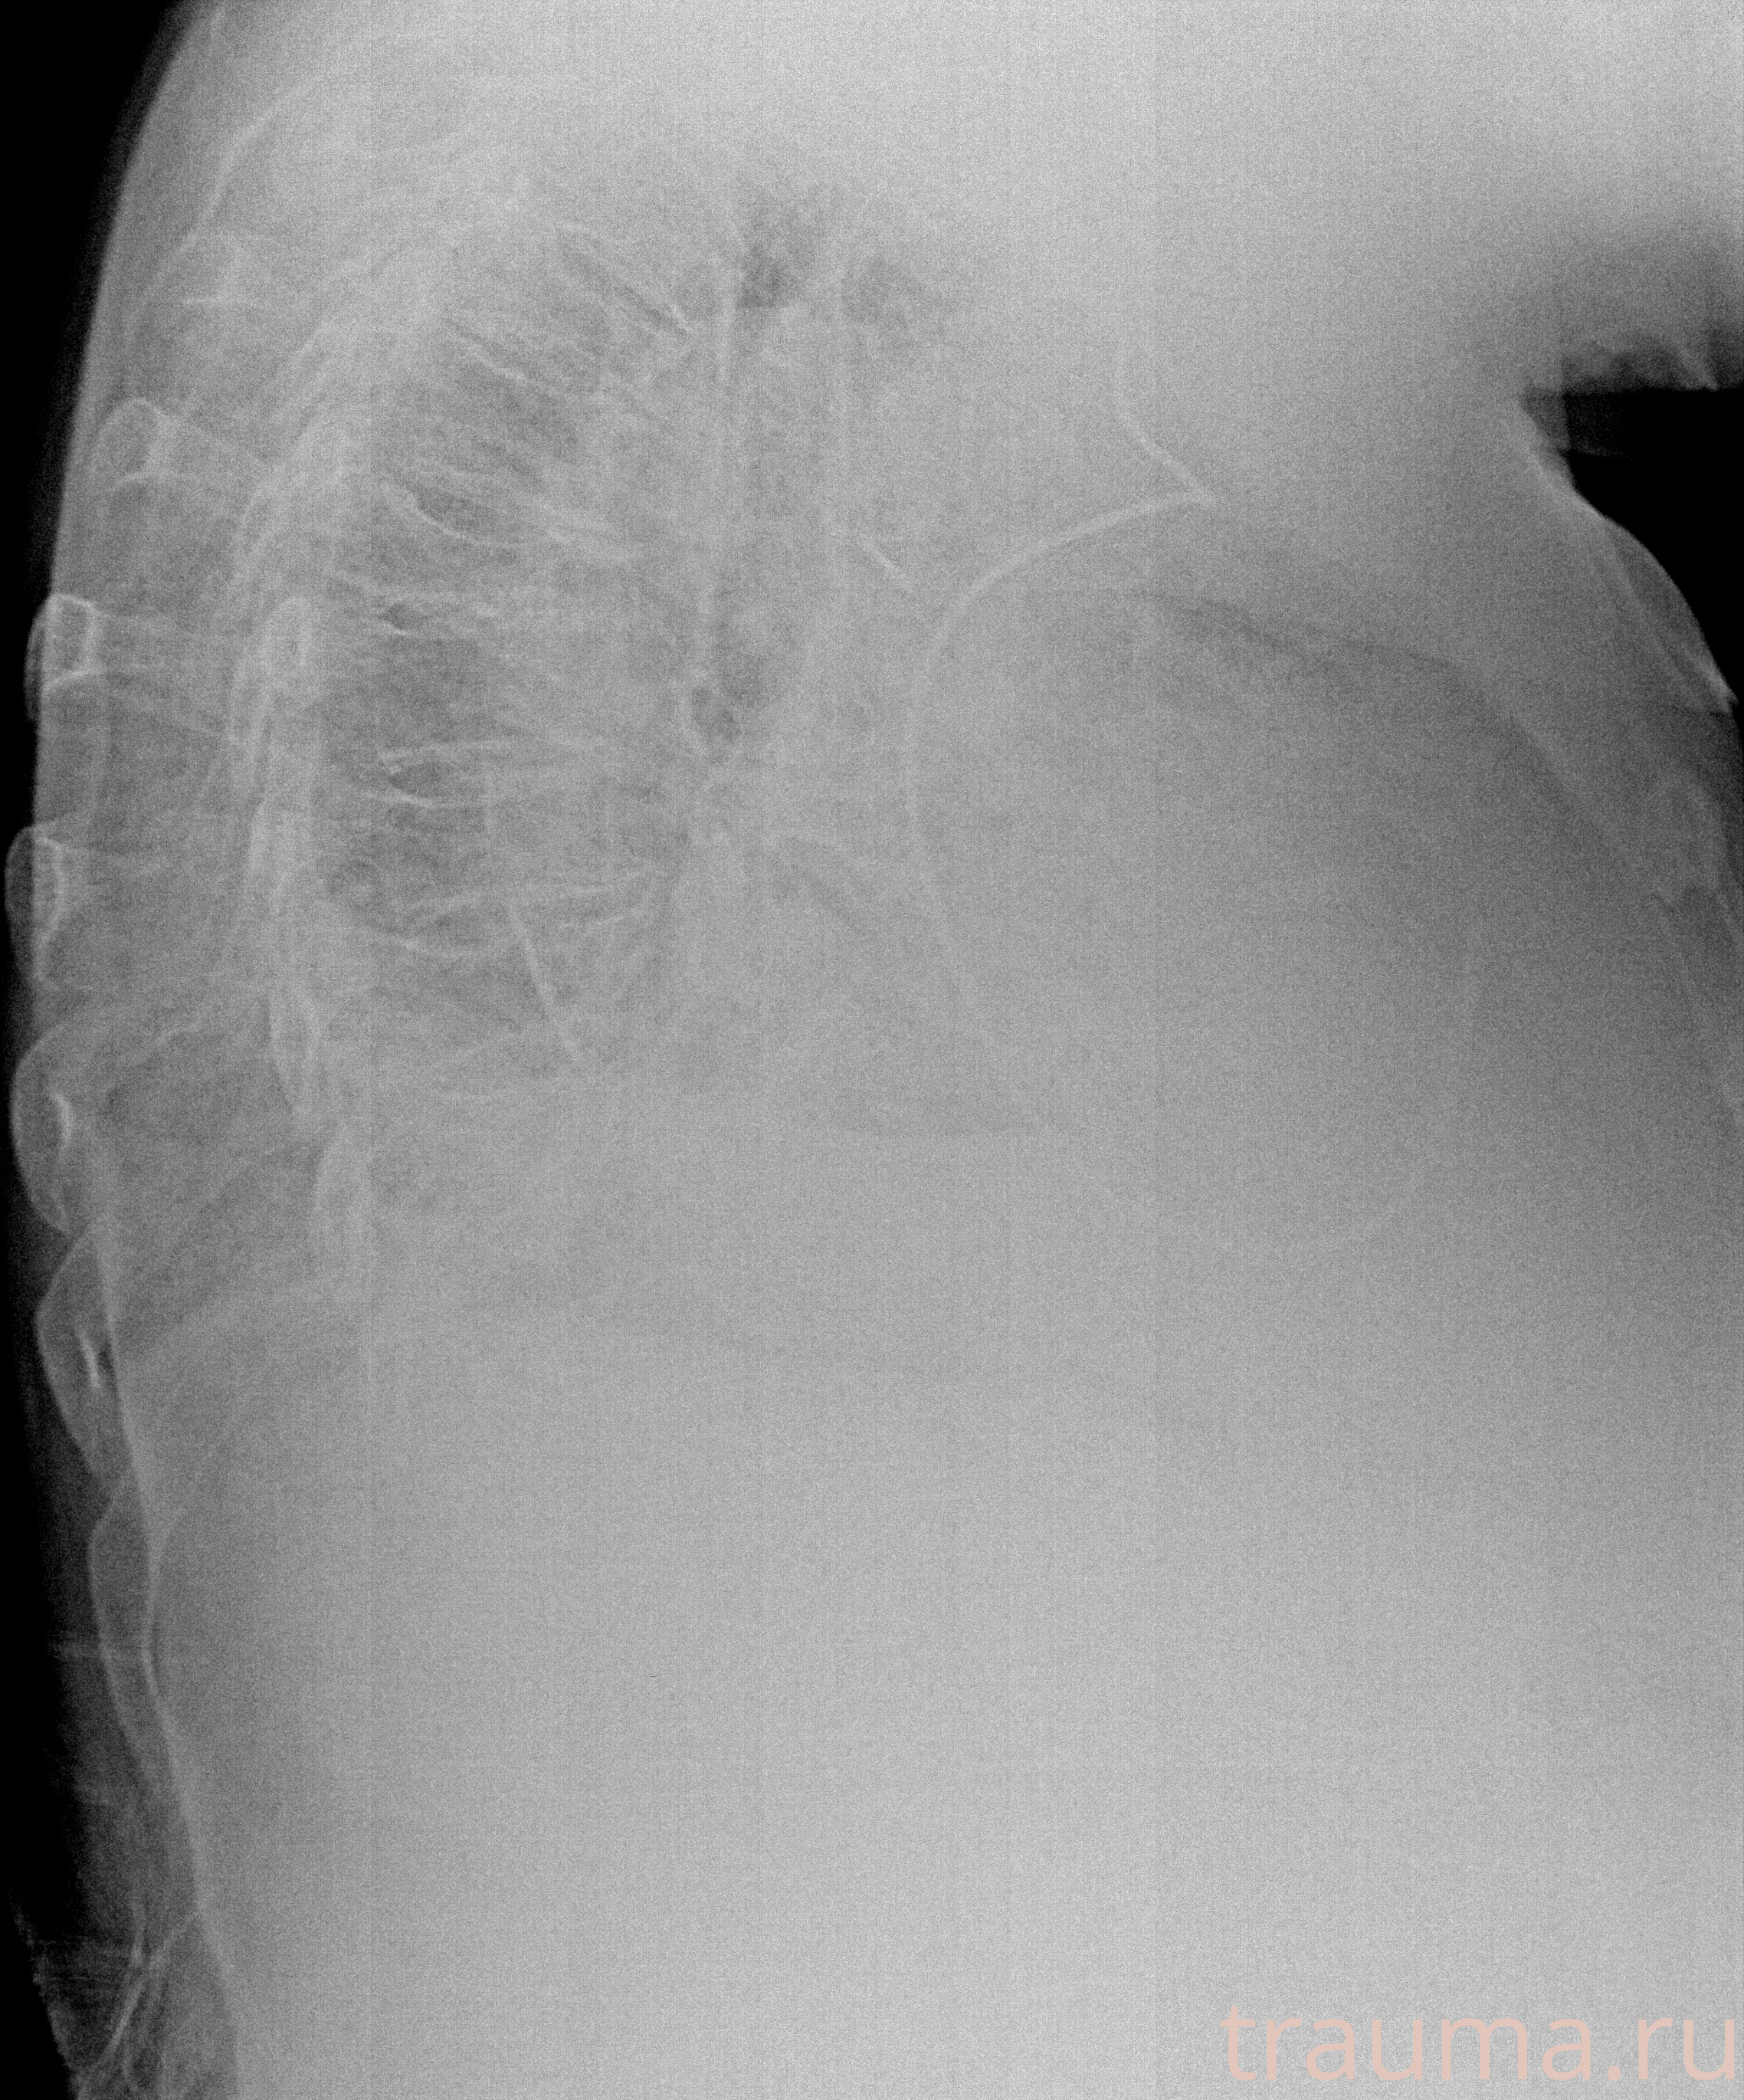

Рентгенограммы

Рентген на дому: по вашему адресу приезжает врач-рентгенолог, травматолог-ортопед с мобильным рентгеновским аппаратом, проводит диагностику травмы или заболевания, делает необходимые рентгенограммы, дает рекомендации по дальнейшему лечению. Получить качественные снимки в домашних условиях возможно благодаря уникальной методике, разработанной МосРентген Центром для института  Склифосовского

Яркость: 1   Контраст: 1   Инвертировать: 0 Увеличение: 1

Перетаскивайте мышь вверх/вниз для контраста, влево/право для яркости. Прокрутка колесом изменяет масштаб. Нажмите Сбросить для возврата к исходному изображению. При увеличении держите мышь в той области, которую хотите рассмотреть.